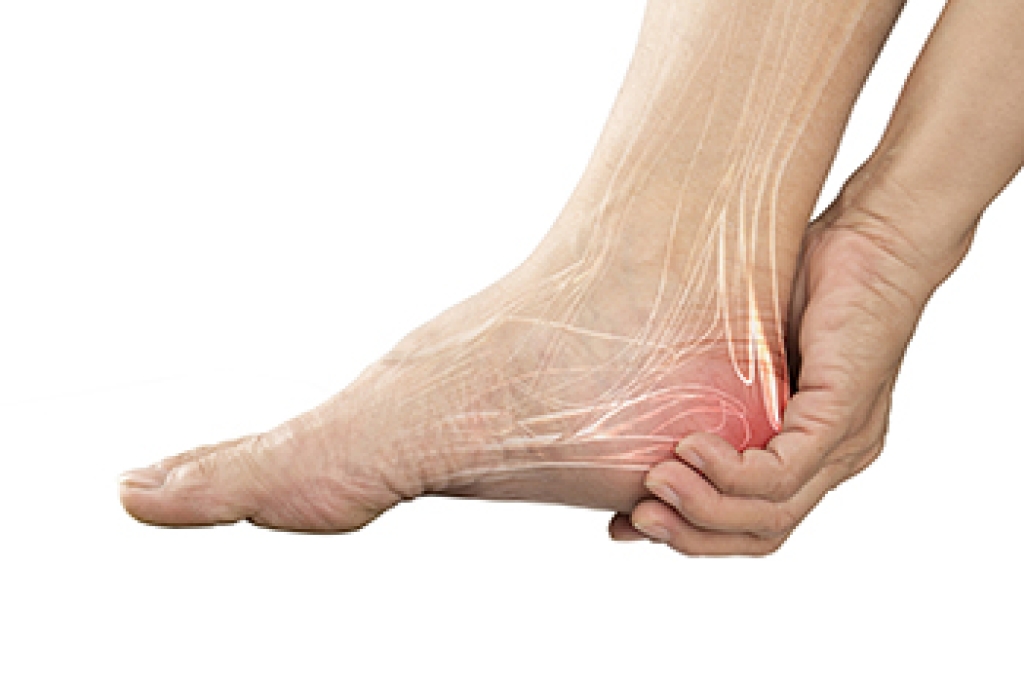

A fifth metatarsal fracture is a break in the long bone on the outside of the foot that connects to the little toe. This injury often occurs after a sudden twist of the foot, a misstep on uneven ground, or direct impact during sports. Patients usually notice sharp pain along the outer side of the foot along with swelling and bruising. Walking may become difficult, and the area can feel tender to the touch. Some fractures occur near the base of the bone and may develop slowly from repeated stress, especially in athletes or active individuals. A podiatrist begins with a careful examination of the foot and reviews how the injury occurred. X-rays are often used to confirm the fracture and determine its exact location. Treatment may include protective immobilization, limited weight bearing, and targeted exercises once healing begins. In certain cases, surgery may be recommended for proper alignment. If you think you may have a foot fracture, it is suggested that you make an immediate appointment with a podiatrist.